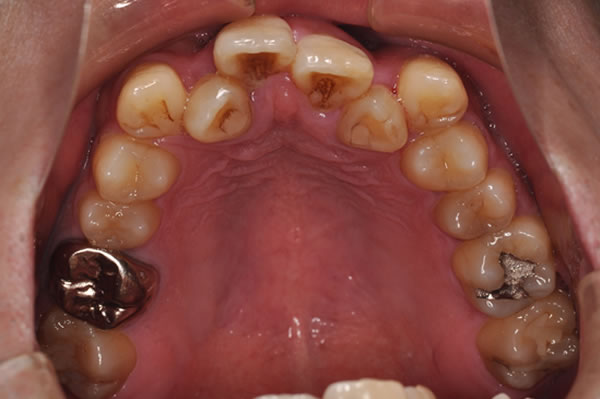

唇側矯正の治療例

反対咬合症例

治療前(初診)

治療後